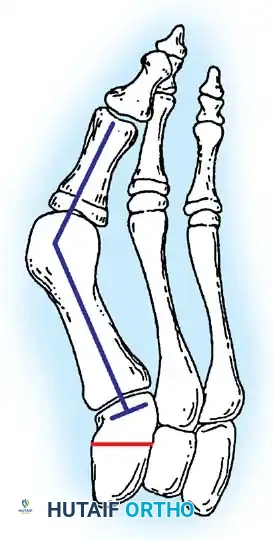

Inadequate vascularity or sensibility should be investigated thoroughly before bunion surgery is considered. In addition, the position of the articular surface of the metatarsal head in relation to the longitudinal axis of the fi rst metatarsal should be determined (Fig. 78-8). Standard preoperative radiographs should include standing dorsoplantar and lateral views, a nonstanding lateral oblique view, and axial sesamoid views (Fig. 78-9). The hallux valgus angle and the fi rst-second intermetatarsal angle should fi rst be drawn on the standing dorsoplantar view by bisecting the shafts of the bones (Fig. 78-10), with an awareness of the normal ranges. These angles are most frequently cited as guidelines for treatment decisions, but Donnelly et al. reported that interobserver measurements of the hallux valgus angle varied by approximately 6 degrees and of the intermetatarsal angle by 4 degrees. They cautioned that potential errors in measurement should be considered when these parameters are used to make treatment decisions. The hallux valgus interphalangeus angle and any evidence of degenerative arthritic changes at the fi rst metatarsophalangeal or metatarsocuneiform joints should be documented. Oddities may be present and, if overlooked, may compromise a technically well-done procedure. Mann emphasized that the presence of an os inter-

Fig. 78-10 Method of measuring hallux valgus angle and intermetatarsal angle. Center points are connected, and intersecting lines defi ne angles.